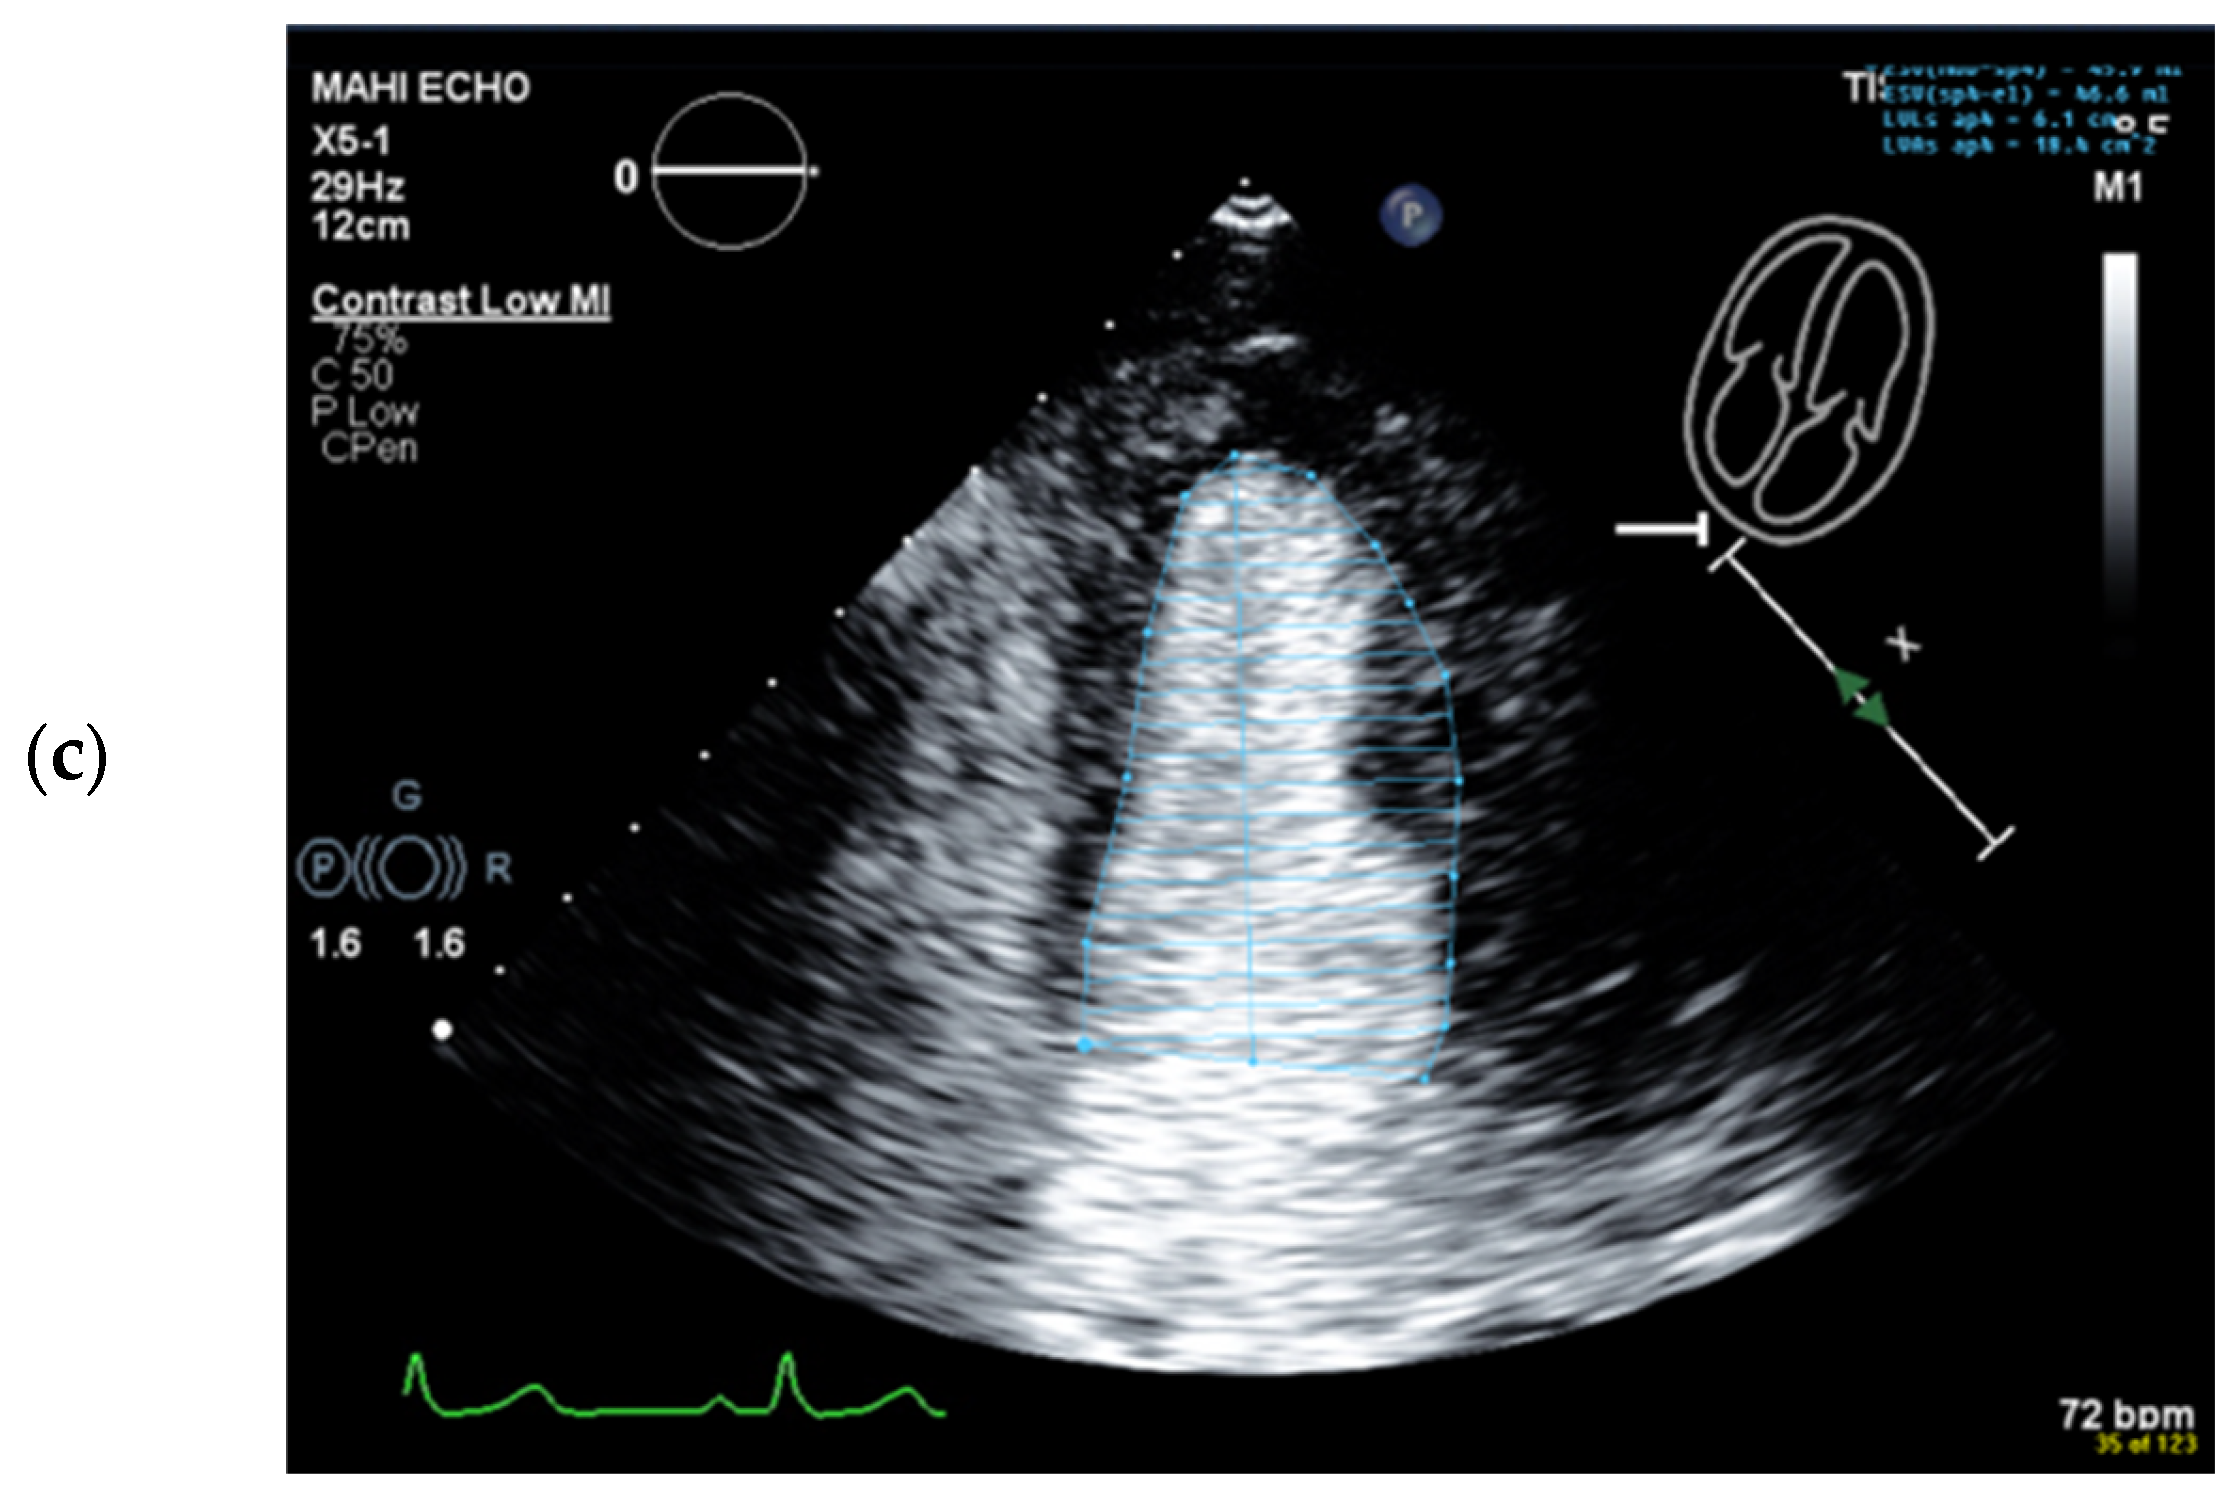

Wrong Contour/Papillary Muscle

| 1 | Select unforeshortened loops avoid 4-chamber views, which include anterolateral papillary muscles | When several loops are available, select the one with the longest long axis which impairs tracing of the lateral LV wall |

| 5 | Trace the LV border: end systole | Starting on the septal mitral ring (4-chamber view) and inferior mitral ring (2-chamber view), following the dark/bright interface until the lateral/anterior mitral ring The start and end points of the contour at the mitral ring should be connected with a straight line |

| 6 | Check the LV length (distance between the middle of the line connecting the mitral ring and the apex) | When the difference in diastolic LV length between 4- and 2-chamber views is <0.5 cm, no major foreshortening can be assumed When the difference is >5 mm, the recording of the view with the shorter LV length is probably not optimal. The other recordings of this view should be reviewed to find the one with the longest LV [59]. |